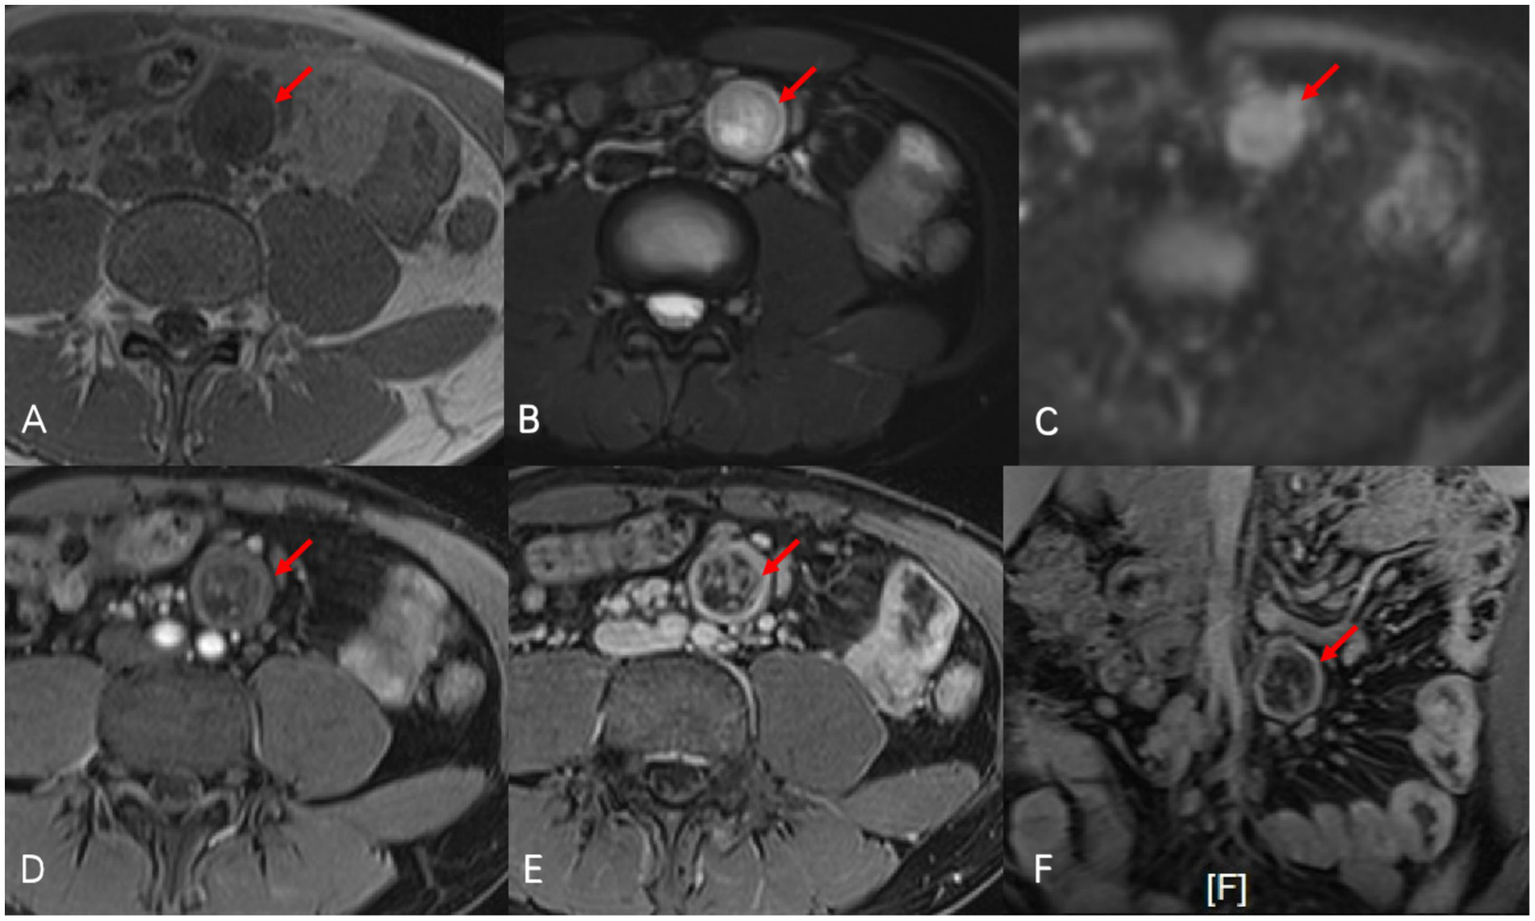

Figure 2

Oval-shaped abnormal signal nodule (red arrow) was observed at the mid-left root of the mesentery in abdominal enhanced MRI. On T1-weighted images (A), the nodule presented as isointense to hypointense, and on fat-suppressed T2-weighted images (B), it showed slightly to markedly higher signals with mixed intensity at the boundaries. The signal is mildly increased on diffusion-weighted imaging (C). After enhancement [(D) arterial phase, (E) portal venous phase, and (F) portal venous phase/coronal], the nodule showed progressive enhancement, with pronounced enhancement at the edges, and a clear cystic change could be seen in the central area.

Two months later, the patient’s symptoms significantly improved with no further fever. CTE on 22 July 2024, showed unchanged thickening and coarsening of the bowel walls, multiple full mesenteric lymph nodes, and a persistent cystic-solid nodule near the left common iliac artery, potentially a schwannoma. Enhanced MRI on 25 July 2024, confirmed these findings, with the nodule resembling an enlarged necrotic lymph node (Figure 2). Due to the unclear pathological diagnosis, tuberculosis, lymphoma, and other diseases could not be excluded, complicating the treatment of Crohn’s disease with biologics or immunosuppressants. MDT discussion on 29 July 2024 recommended surgical resection over percutaneous biopsy due to potential risks and complications. Surgery revealed a hard, smooth nodule (3 × 3 cm) in the mesentery above the left iliac artery. Preliminary pathology suggested a spindle cell tumor, and immunohistochemistry on 8 August 2024, confirmed it as a schwannoma with the following features: CD117 (−), CD34 (−), DOG-1 (−), SMA (−), S-100 (+), Desmin (−), Ki67 (+ 1%), SDHB (+), EMA (−), and BRAF (−) (Figure 3). The patient recovered well after surgery and was initiated on ustekinumab therapy for Crohn’s disease. Follow-up evaluations at 6 months and 1 year revealed no signs of schwannoma recurrence, with slight improvement in Crohn’s disease compared to the pre-treatment status.

MRI is also essential for diagnosing mesenteric schwannomas, with low signal intensity on T1-weighted images and high signal intensity on T2-weighted images (2, 5, 10–12). Gadolinium-enhanced MRI reveals the tumor’s vascularity, aiding differentiation from other tumor (9, 13). Despite the characteristic MRI features, other tumors may exhibit similar signals, making preoperative diagnosis challenging. In our case, MRI suggested the possibility of enlarged necrotic lymph nodes.